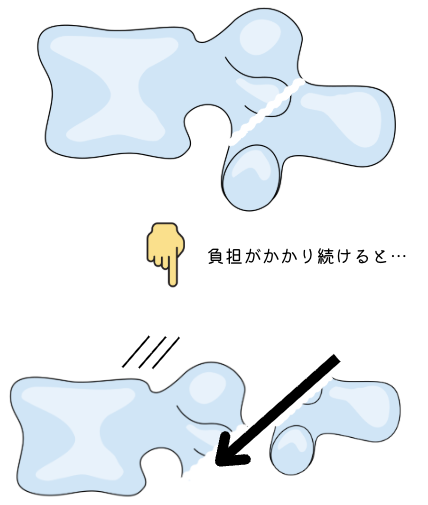

何より防ぐべき「分離すべり症」

みなさんは「腰椎すべり症」という疾患を聞いたことはあるでしょうか?60~70代で特に多くなる腰のけがです。これは加齢によって腰のクッションがすり減ってしまったり、筋力が低下して起こるものなのですが、分離症を放っておくと10代からすべり症が完成してしまいます。

分離症が起こっている場所は骨同士が支え合うことができないため、負担がかかり続けると雪崩のように骨のずれが発生してしまいます。

イラストのすべりはかなり大袈裟ですが、このように滑らないよう周りの筋肉が過度に働き腰痛を引き起こしたり、靭帯や神経を傷つけてしまいます。